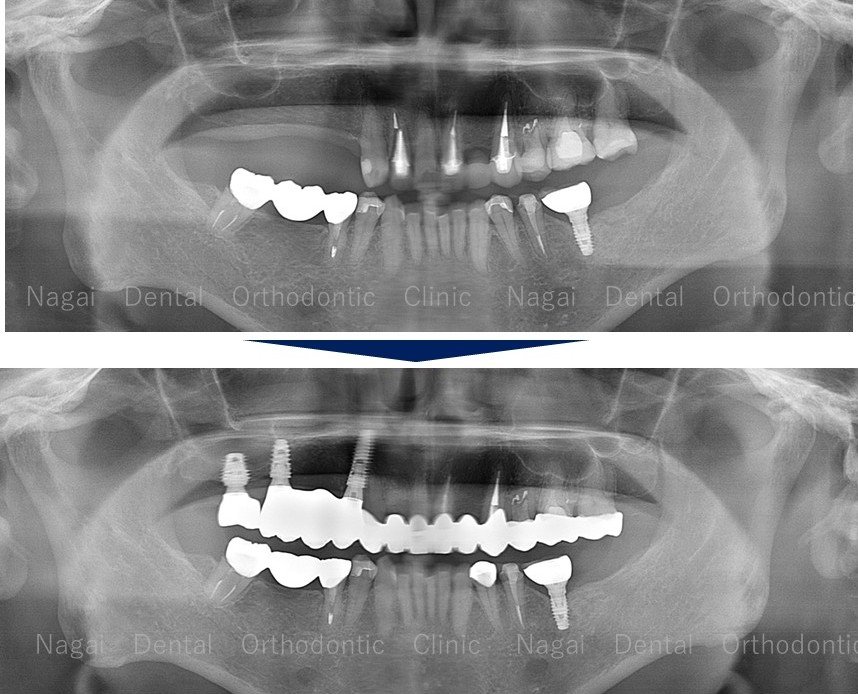

【口腔内の詳細変化】

▲再構築を目的とした治療を行いました

▲欠損していた左上奥歯部分の補綴完了状態

▲支持の安定が期待される治療を行いました

| 治療内容 | 上下オールオン4 |

| 年齢/性別 | 70代/男性 |

| 背景 | 既存補綴物の脱離と広範囲な欠損を主訴に来院。上下顎ともに「オールオン4」を採用し、骨造成を最小限に抑えつつ即日の機能回復を図りました。チタンフレームとジルコニアに加え、歯肉部分も精巧に再現することで自然な口元を構築。安定した噛み合わせにより、食事や会話を心から楽しめる日常を取り戻されました。 |

| 治療期間 | 約16か月(通院8回) |

| 費用 | 6,357,780円(税込) |